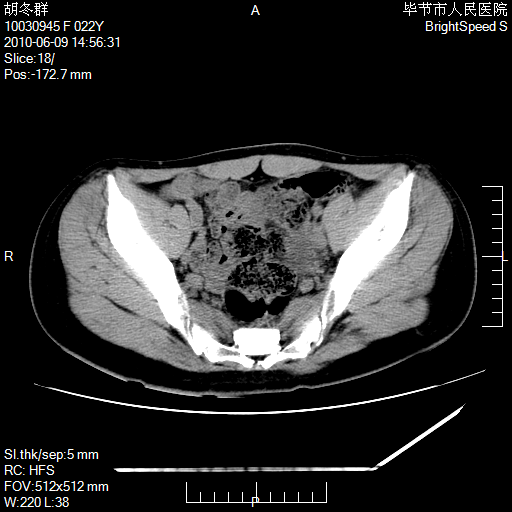

患者23岁,发现腹部包块3月。

左侧卵巢囊腺瘤或囊腺癌

盆腔内囊性占位性病变;考虑左侧卵巢囊腺瘤。

有分隔、壁薄,支持考虑左侧卵巢囊腺瘤。

左侧卵巢浆液性囊腺瘤。

支持考虑左侧卵巢囊腺瘤;宫腔积液。

有分隔、壁薄,支持考虑左侧卵巢囊腺瘤。排尿后,膀胱缩小,由于重力作用,肿块下移就到了膀胱位置,很好理解。